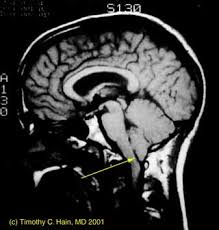

La malformación de Chiari consiste en un desplazamiento hacia abajo de la porción caudal del cerebelo y, a veces, del tronco cerebral, que se encuentran situados por debajo del foramen magno (3 mm por debajo de este foramen en el examen con resonancia magnética RM).

Clínicamente puede ser difícil de diferenciar de una esclerosis múltiple, especialmente cuando la malformación del tejido cerebral se presenta en ausencia de cambios óseos significativos. El método ideal para aclarar cualquiera de estos planteos diagnósticos es la imagen de resonancia magnética.